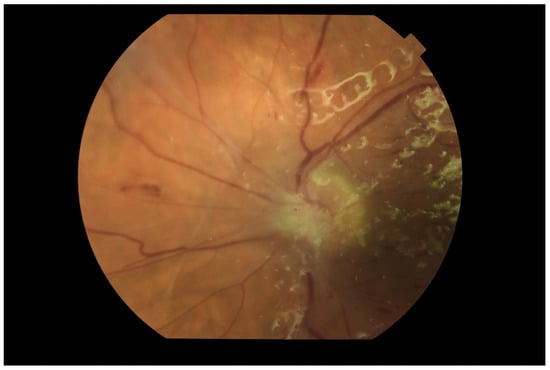

The tendency to abscess formation in the course of Klebsiella infection is also reflected in eye. One of the rare but characteristic feature of EE in the course of Klebsiella infection is the formation of subretinal abscesses [26]. They take the form of retinal elevation and paleness (Figure 1 and Figure 2). With properly selected antibiotic therapy, even large abscesses may be absorbed. If the patient is undergoing vitrectomy, intraoperative drainage may be considered [27].

Figure 1.

Fundus pictures of subretinal abscess, taken on the second day after vitrectomy. Partially drained abscess is visible, located nasally from the optic disc. Poor image quality is caused by the presence of inflammatory cells in the anterior chamber.